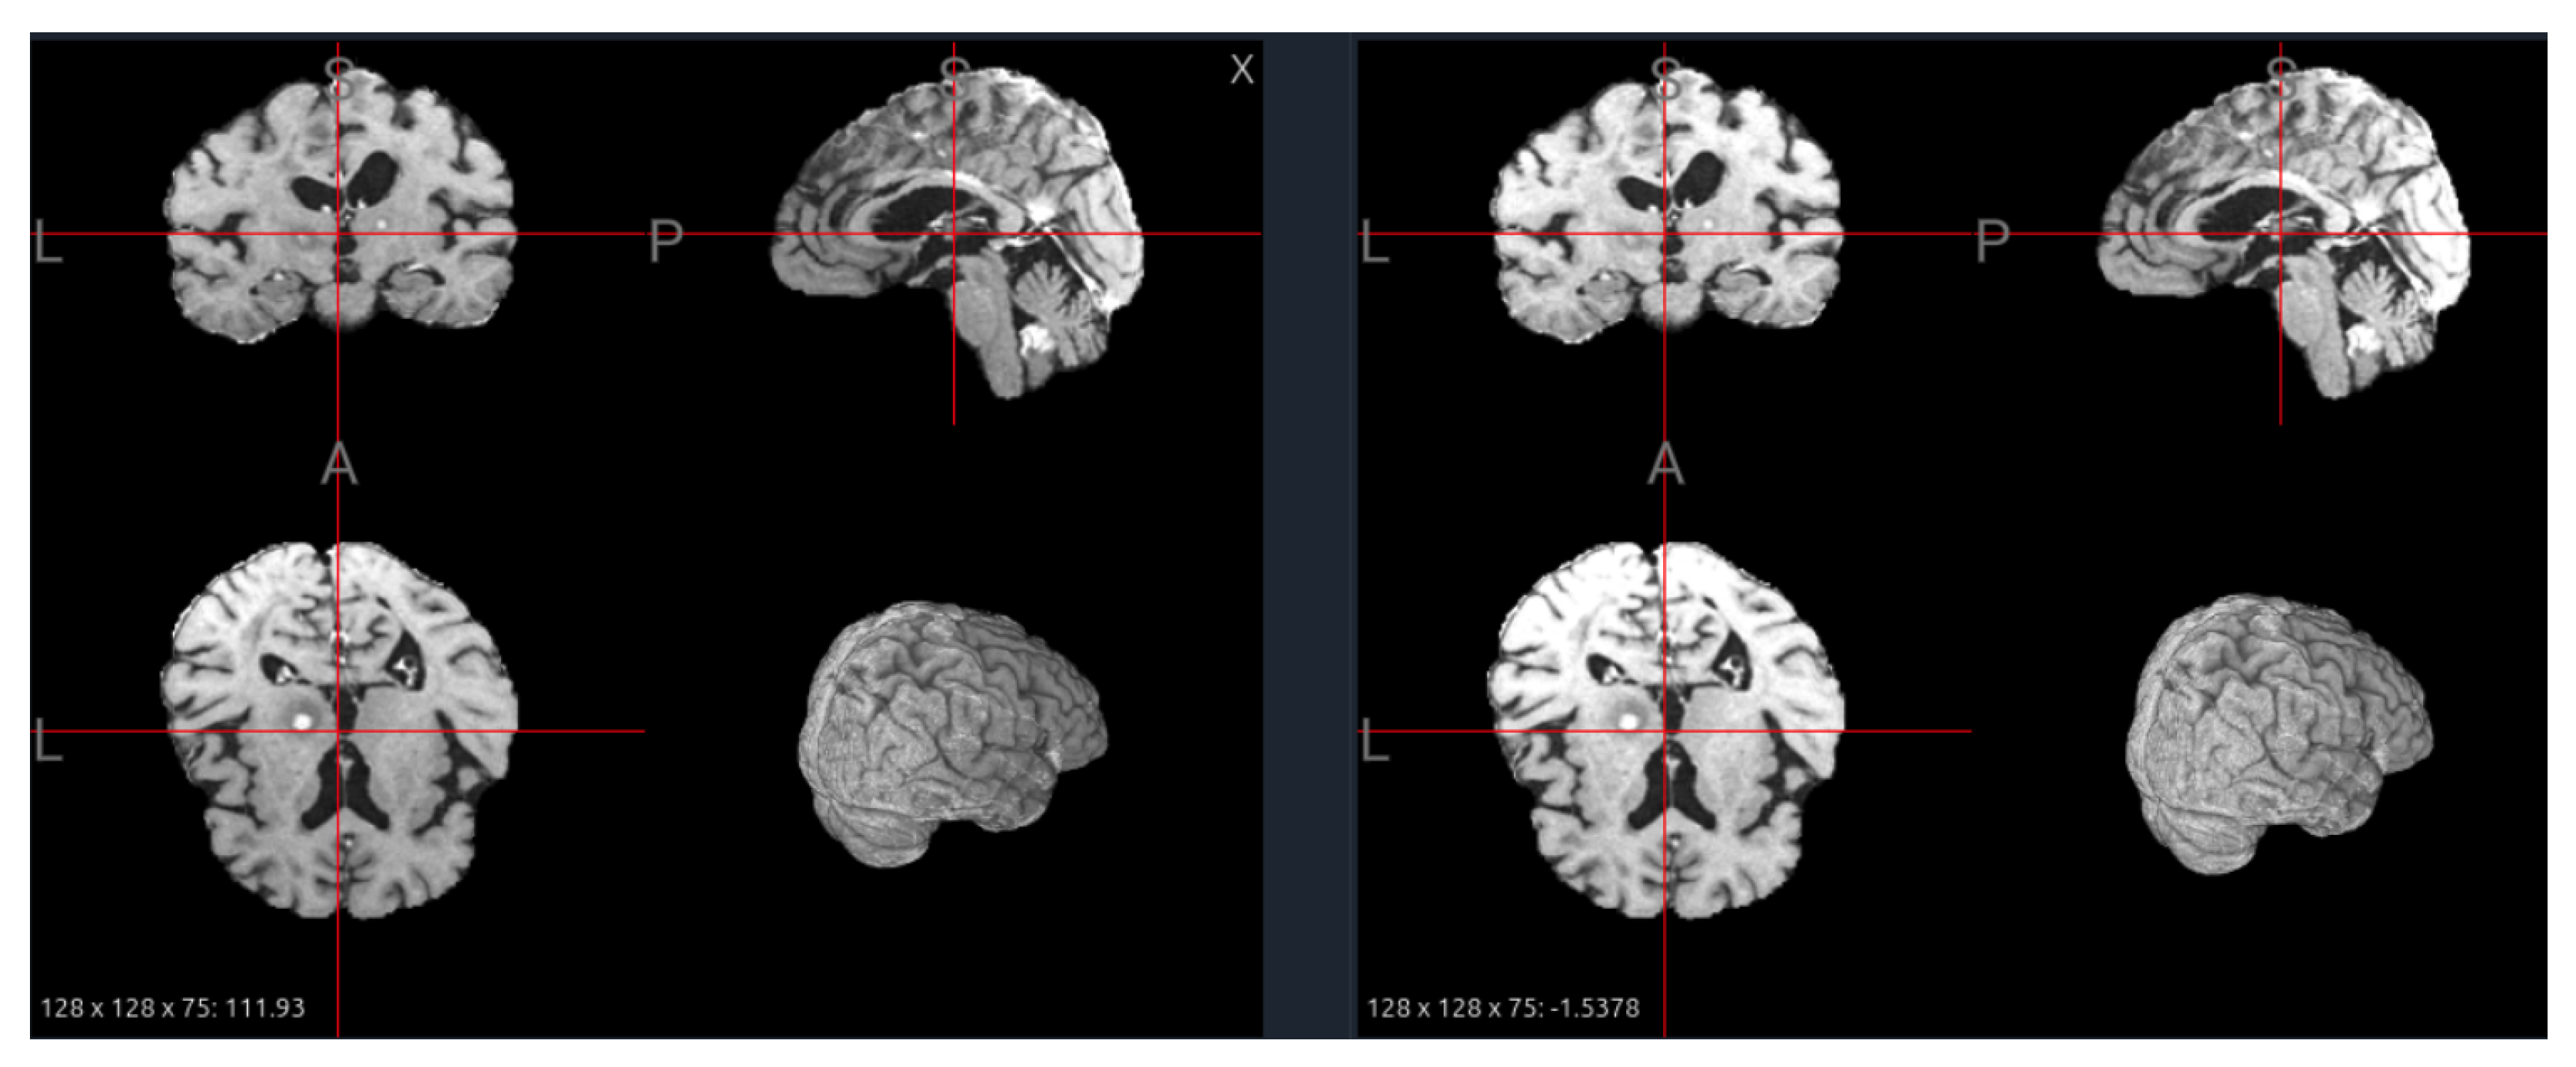

6.3. Skull Stripping

The primary goal of skull stripping is to remove non-brain tissue, such as the skull, scalp, and dura mater, from the image. This is a critical step as these tissues have high-intensity signals that can interfere with intensity normalization and confuse segmentation algorithms. Common tools include FSL’s Brain Extraction Tool (BET) [34], AFNI’s 3dSkullStrip [35], and more recently, deep learning-based methods like HD-BET [36], which often provide more accurate results. While most datasets in our analysis are provided pre-stripped (e.g., BraTS, ISLES22), the specific algorithm used often varies or is not documented, leading to subtle differences in the final brain mask. Figure 9 illustrates the effect of skull stripping on a PD image from the IXI dataset, where non-brain tissues such as the scalp and skull are successfully removed, leaving only the intracranial structures for further analysis.

From a foundation model standpoint, skull stripping can influence both pretraining and downstream transfer. When training models across multiple datasets, consistent skull stripping helps reduce non-biological variability and ensures that the model focuses on relevant brain structures. However, inconsistency across datasets—where some scans are stripped and others are not—can lead to feature-space fragmentation, causing the model to learn dataset-specific biases rather than generalizable brain representations. Therefore, strict harmonization of preprocessing pipelines, including identical skull stripping tools, thresholds, and quality-control procedures, is essential.

Moreover, the choice to strip or retain the skull should align with the model’s target scope. For models designed to capture brain-centric features—such as lesion segmentation, cortical parcellation, or morphometric analysis—skull stripping is generally beneficial, as it directs attention to intracranial tissues. Conversely, for models intended to generalize across multi-modal or multi-organ contexts (e.g., MRI–CT alignment, PET fusion, or structural-to-functional transfer), removing the skull can limit cross-modality correspondence and reduce anatomical completeness. A practical strategy for large-scale foundation model pretraining is to include both stripped and unstripped variants of each scan and use metadata tags or preprocessing embeddings to inform the model about their origin. This dual representation encourages robustness to preprocessing differences and enables the model to learn invariance to skull presence—an increasingly important capability for generalizable medical foundation models.